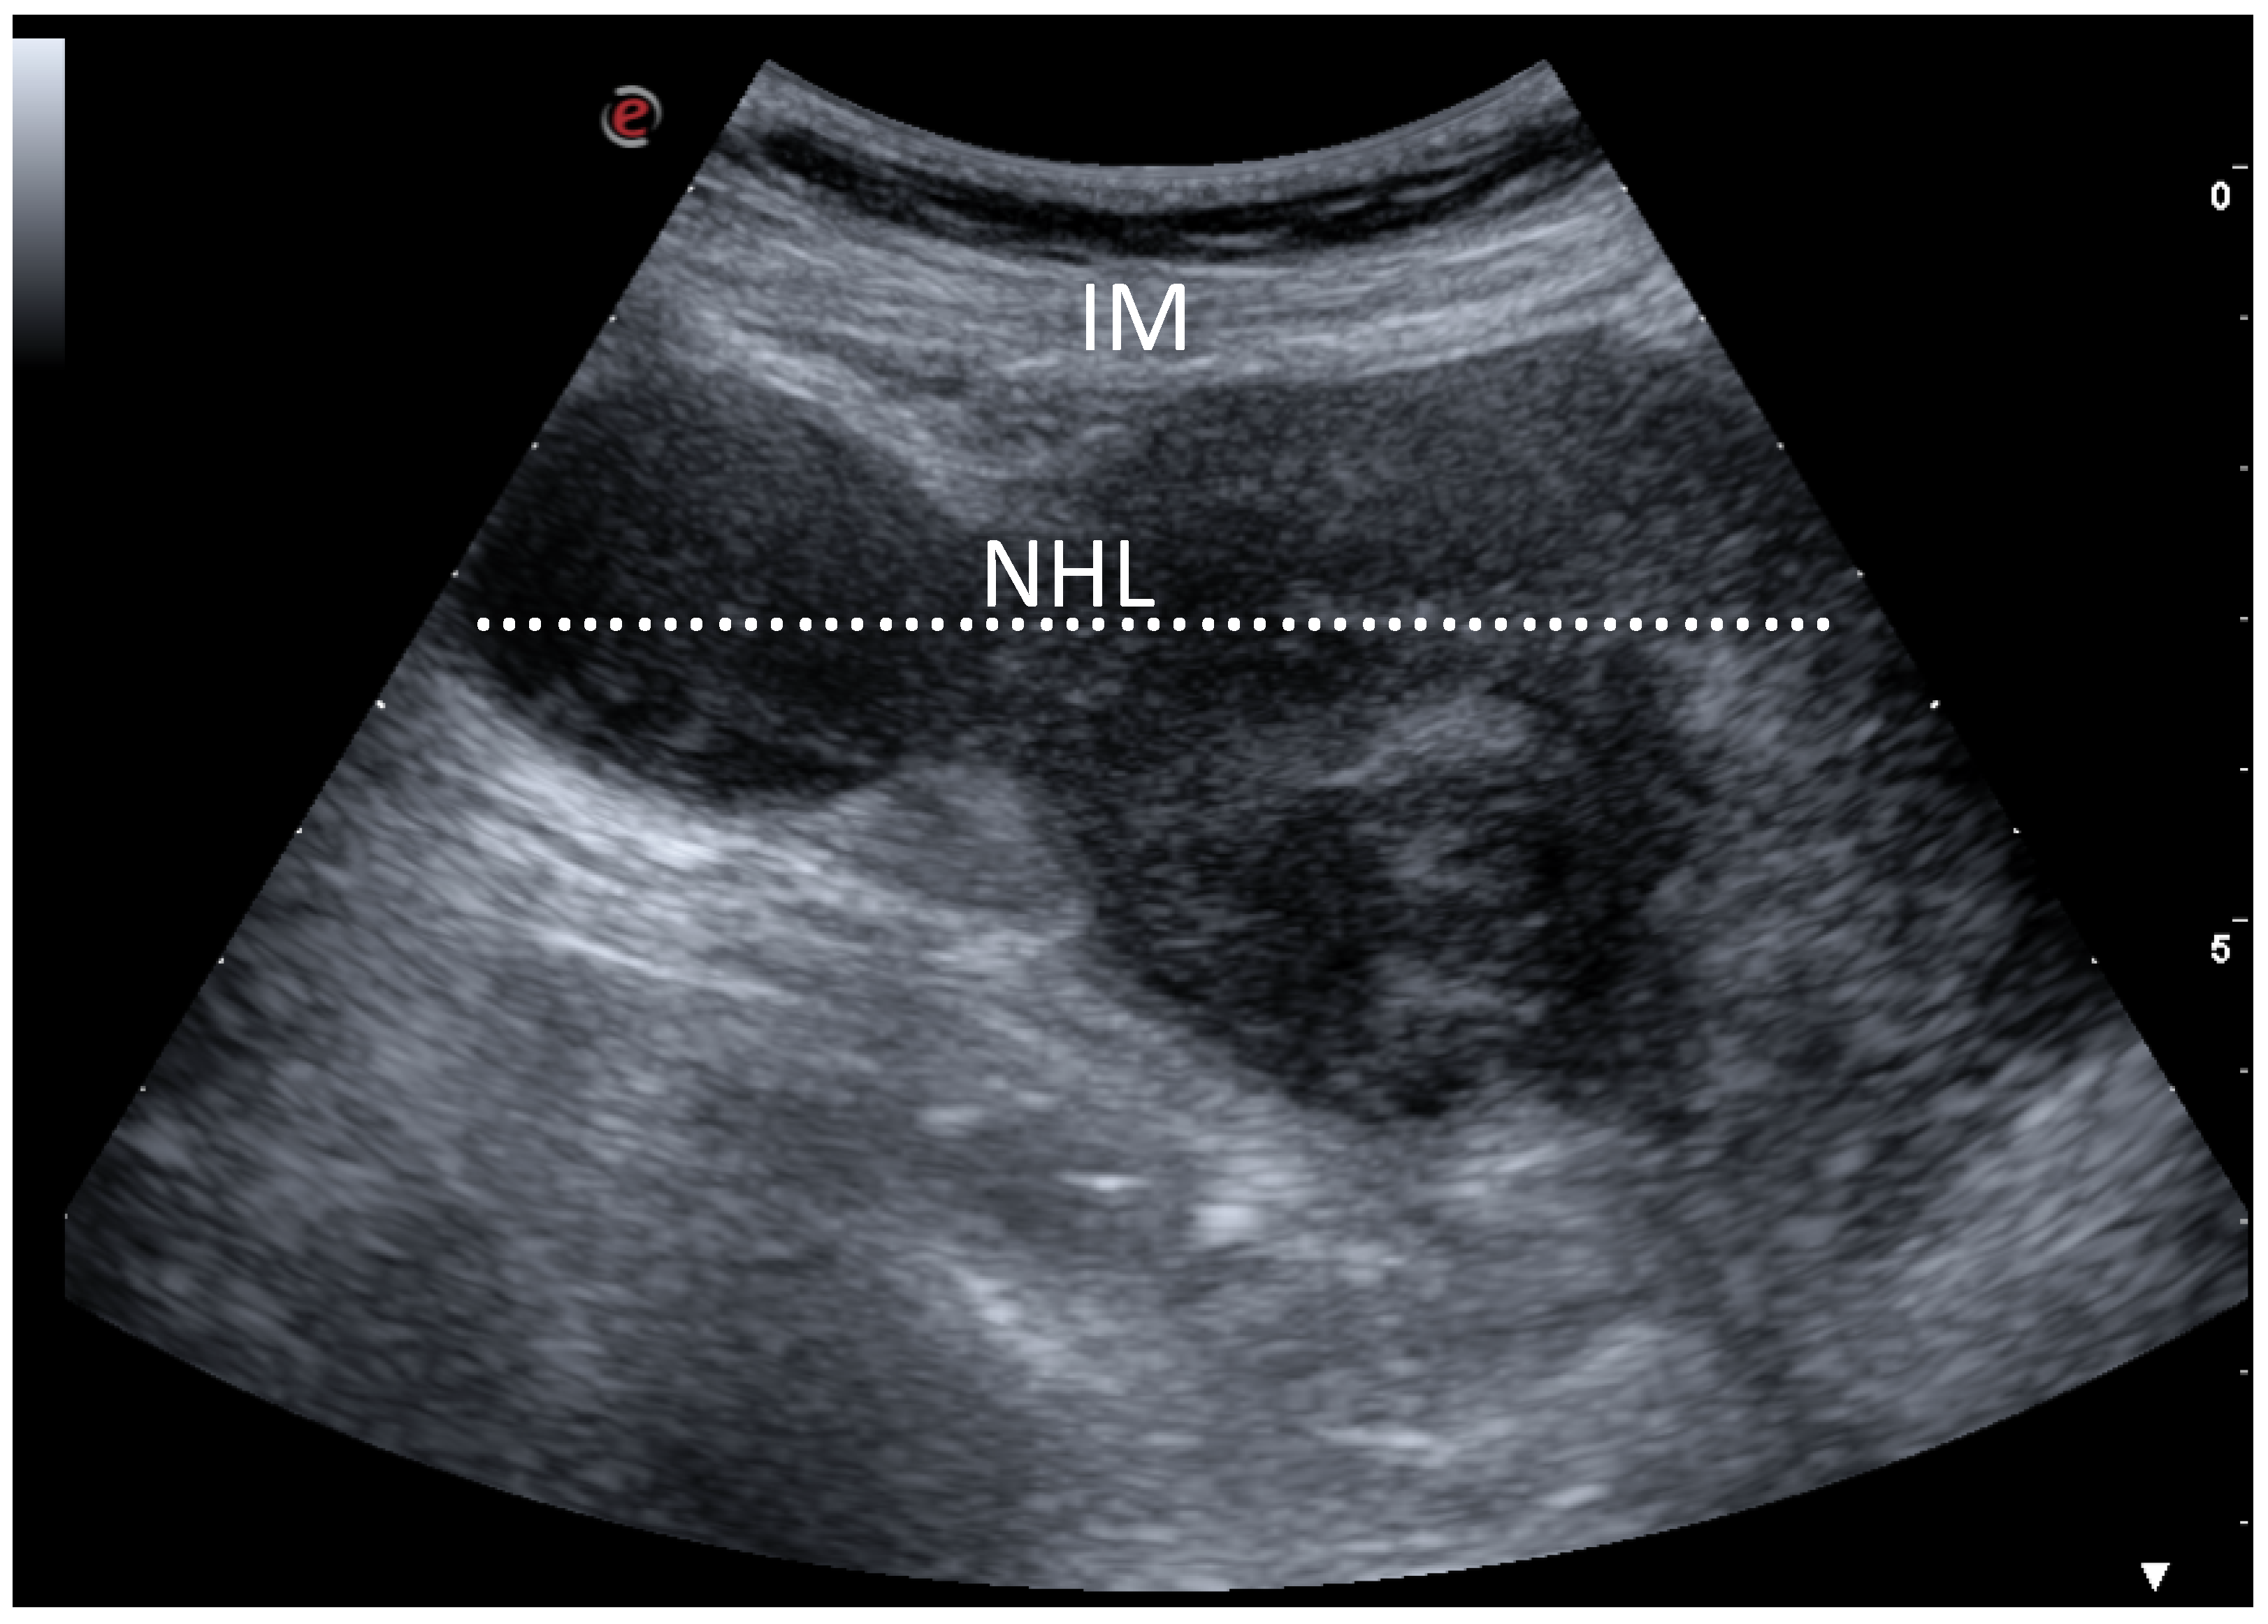

Ultrasonography and Surgical Procedure